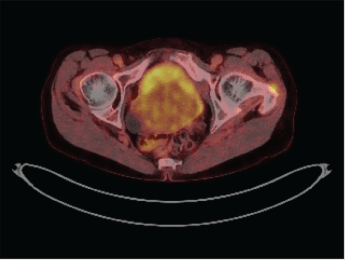

Subsequently, a PET-CT scan of the abdomen and pelvis was performed, which revealed diffusely thickened bladder walls with a moderate uptake of the bladder (Figure 2). There was no sign of paravesical fat infiltration and no pelvic or abdominal lymph node enlargement or any other anomaly. Due to the highly invasive nature of the tumour, bone marrow biopsy was performed. It showed no evidence of leukaemia or lymphoma.

Figure 2: Pet-Scan revealed diffuse thickened, metabolic active bladder walls. View Figure 2